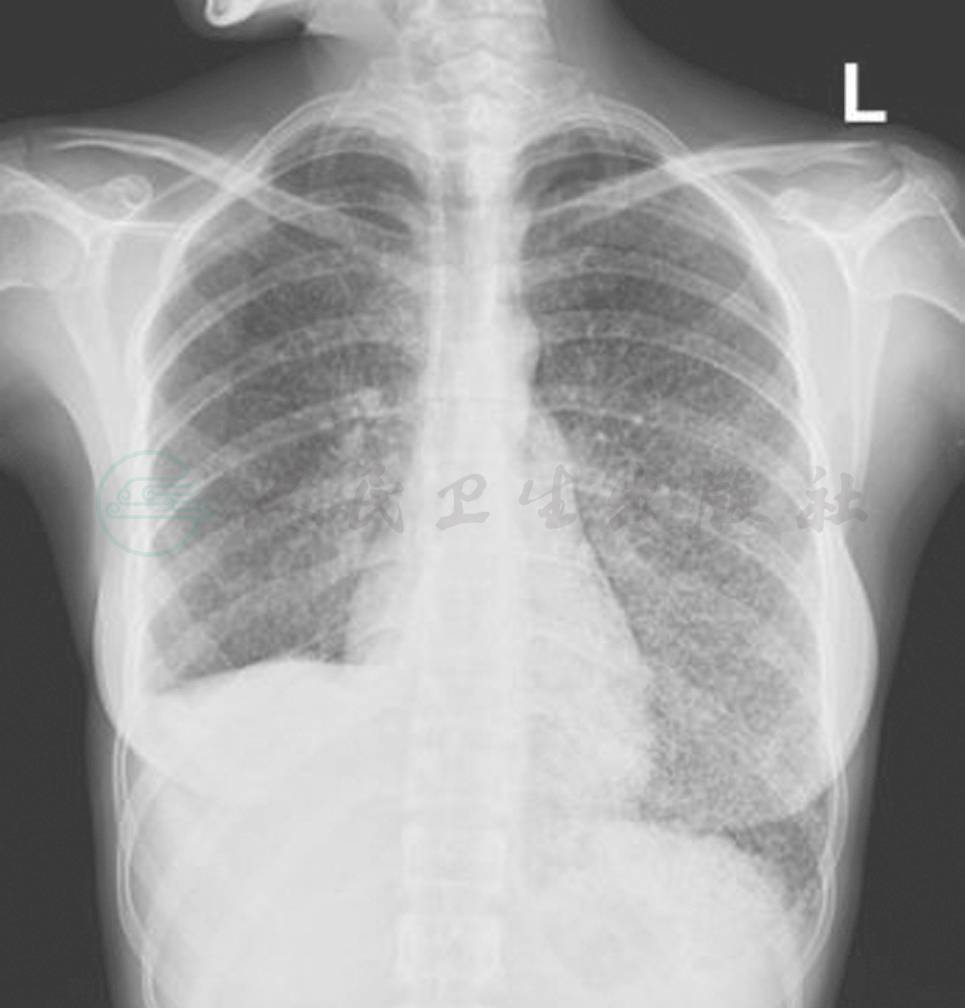

血常规(图3)、尿常规(图4)、粪常规(图5)、血生化(图6)、肿瘤标记物(图7)、感染相关指标(图8)、风湿指标(图9)、胸部平片(图10)、胸部 CT(图11)。

图10 辅助检查(胸部平片2012-01-08)